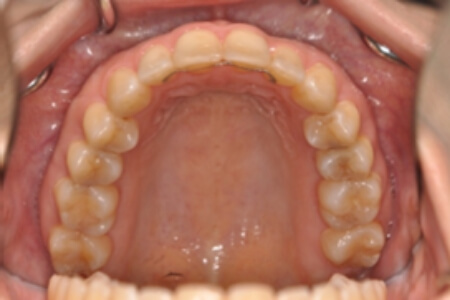

動的治療終了時

症例 症例 症例 症例

治療としては、非抜歯の上、セルフライゲーションブラケット装置(デーモンシステム)とマウスピース矯正装置(インビザライン)で歯の配列を行いました。

同時に顎間ゴムにて咬合関係の改善を行いました。

治療期間は2年11か月でした。